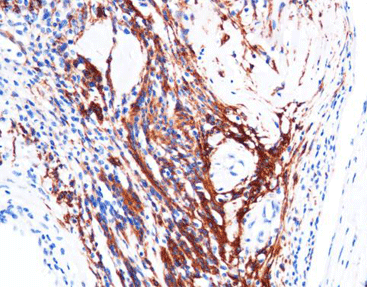

[As Figure shows]

Schwannoma tissue stained with GFAP